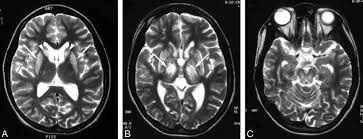

6 8 Neurologic WD is one of the main forms of the disease. In Wilson disease WD T2T2weighted T2w MRI frequently shows hypointensity in the basal ganglia that is suggestive of paramagnetic deposits. It is currently unknown whether this hypointensity is related to copper or iron deposition.

Interval changes on follow-up MR imaging were also closely correlated with clinical findings and. MRI of the brain appears to be more sensitive than CT scanning in detecting early lesions of Wilson disease. The face of the giant panda sign panda sign of the midbrain or double-panda sign is a characteristic pandas face appearance in magnetic resonance imaging MRI images of people with Wilsons disease.

The neurologist was looking for typical symptoms. Wilson disease also known as hepatolenticular degeneration is a multisystem disease due to abnormal accumulation of copper. It is characterized by early onset liver cirrhosis with CNS findings most frequently affecting the basal ganglia and midbrain.

1 In addition a second miniature panda face can be seen in the high signal abnormality in the pons figure C. To describe the spectrum of brain abnormalities in Wilson disease hepatolenticular degeneration as depicted at magnetic resonance MR imaging and computed tomography CT and to relate these findings to neurologic and hepatologic abnormalities.

To describe the spectrum of brain abnormalities in Wilson disease hepatolenticular degeneration as depicted at magnetic resonance MR imaging and computed tomography CT and to relate these findings to neurologic and hepatologic abnormalities. Positive findings believed secondary to this condition were found in 15 subjects. It is found worldwide with a prevalence of approximately 1 case in 30000 live births in most populations. Thirty-eight patients with biochemically proven Wilsons disease underwent magnetic resonanceimaging MRI of the brain as well as neurological examinations. Fifty patients with Wilson disease participated in the cross-sectional. The face of the giant panda sign panda sign of the midbrain or double-panda sign is a characteristic pandas face appearance in magnetic resonance imaging MRI images of people with Wilsons disease. 1 In addition a second miniature panda face can be seen in the high signal abnormality in the pons figure C.